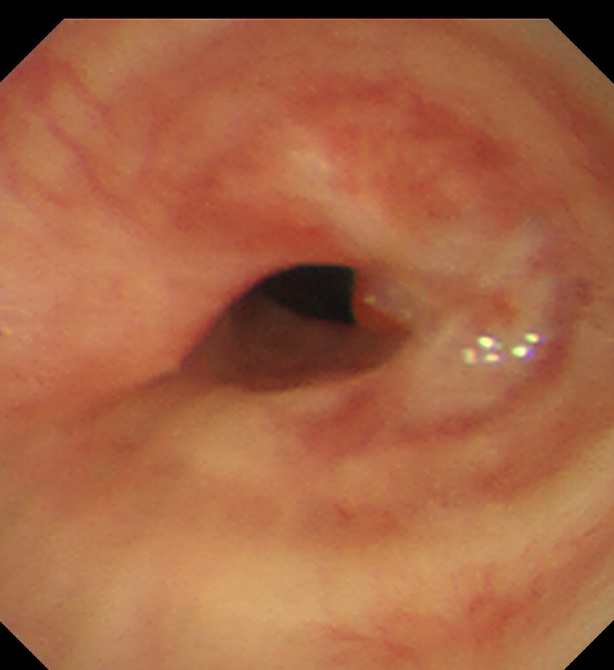

患者,女,50岁,因“外伤后呼吸困难2月”来到昆明医科大学第二附属医院全科医学科治疗。患者2月前因外伤致气管撕裂,在当地医院行气管修补术,术后出现进行性加重呼吸困难。患者来到我院住院后,稍微活动就会感到气促,已不能活动,肺功能显示重度阻塞性肺通气功能障碍,胸部CT显示气管下段重度狭窄,支气管镜检查显示气管下段距隆突2cm处重度瘢痕狭窄,最窄处仅4mm,随时都会发生窒息甚至猝死,手术迫在眉睫!

气管下段狭窄治疗前